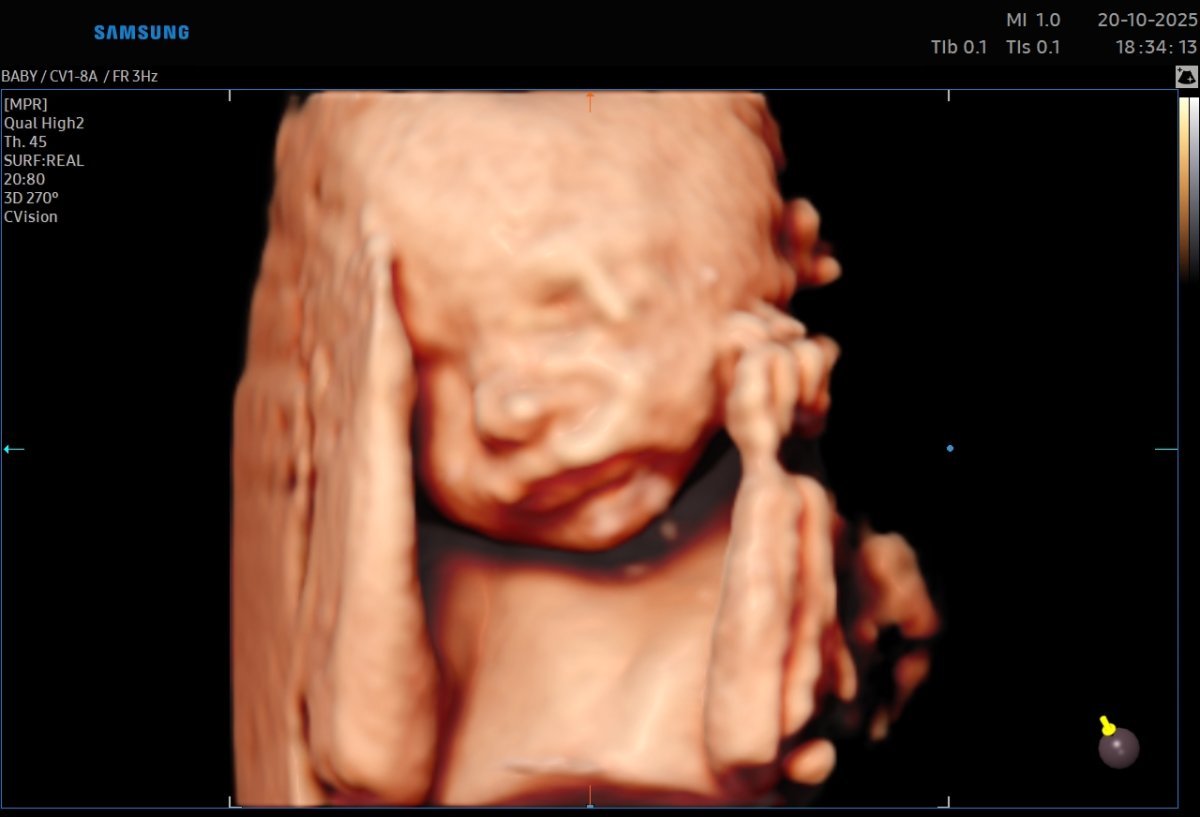

Gallerie de photos